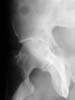

The iliac oblique reveals a displaced fracture of the posterior column, and it appears that the femoral head is not congruous with the acetabulum.

The CT scan confirms what the iliac oblique showed - the acetabulum is incongruous, and the femoral head is following the caudal piece medially. The other thing the femoral head is doing is grinding up against that displaced fracture. This is going to lead to erosion of the femoral head cartilage, and rapid onset of post-traumatic arthritis.

How long will it take? I've seen it happen in less than a year.

Yes it does. The CT scan reveals a fracture through the weight bearing dome.